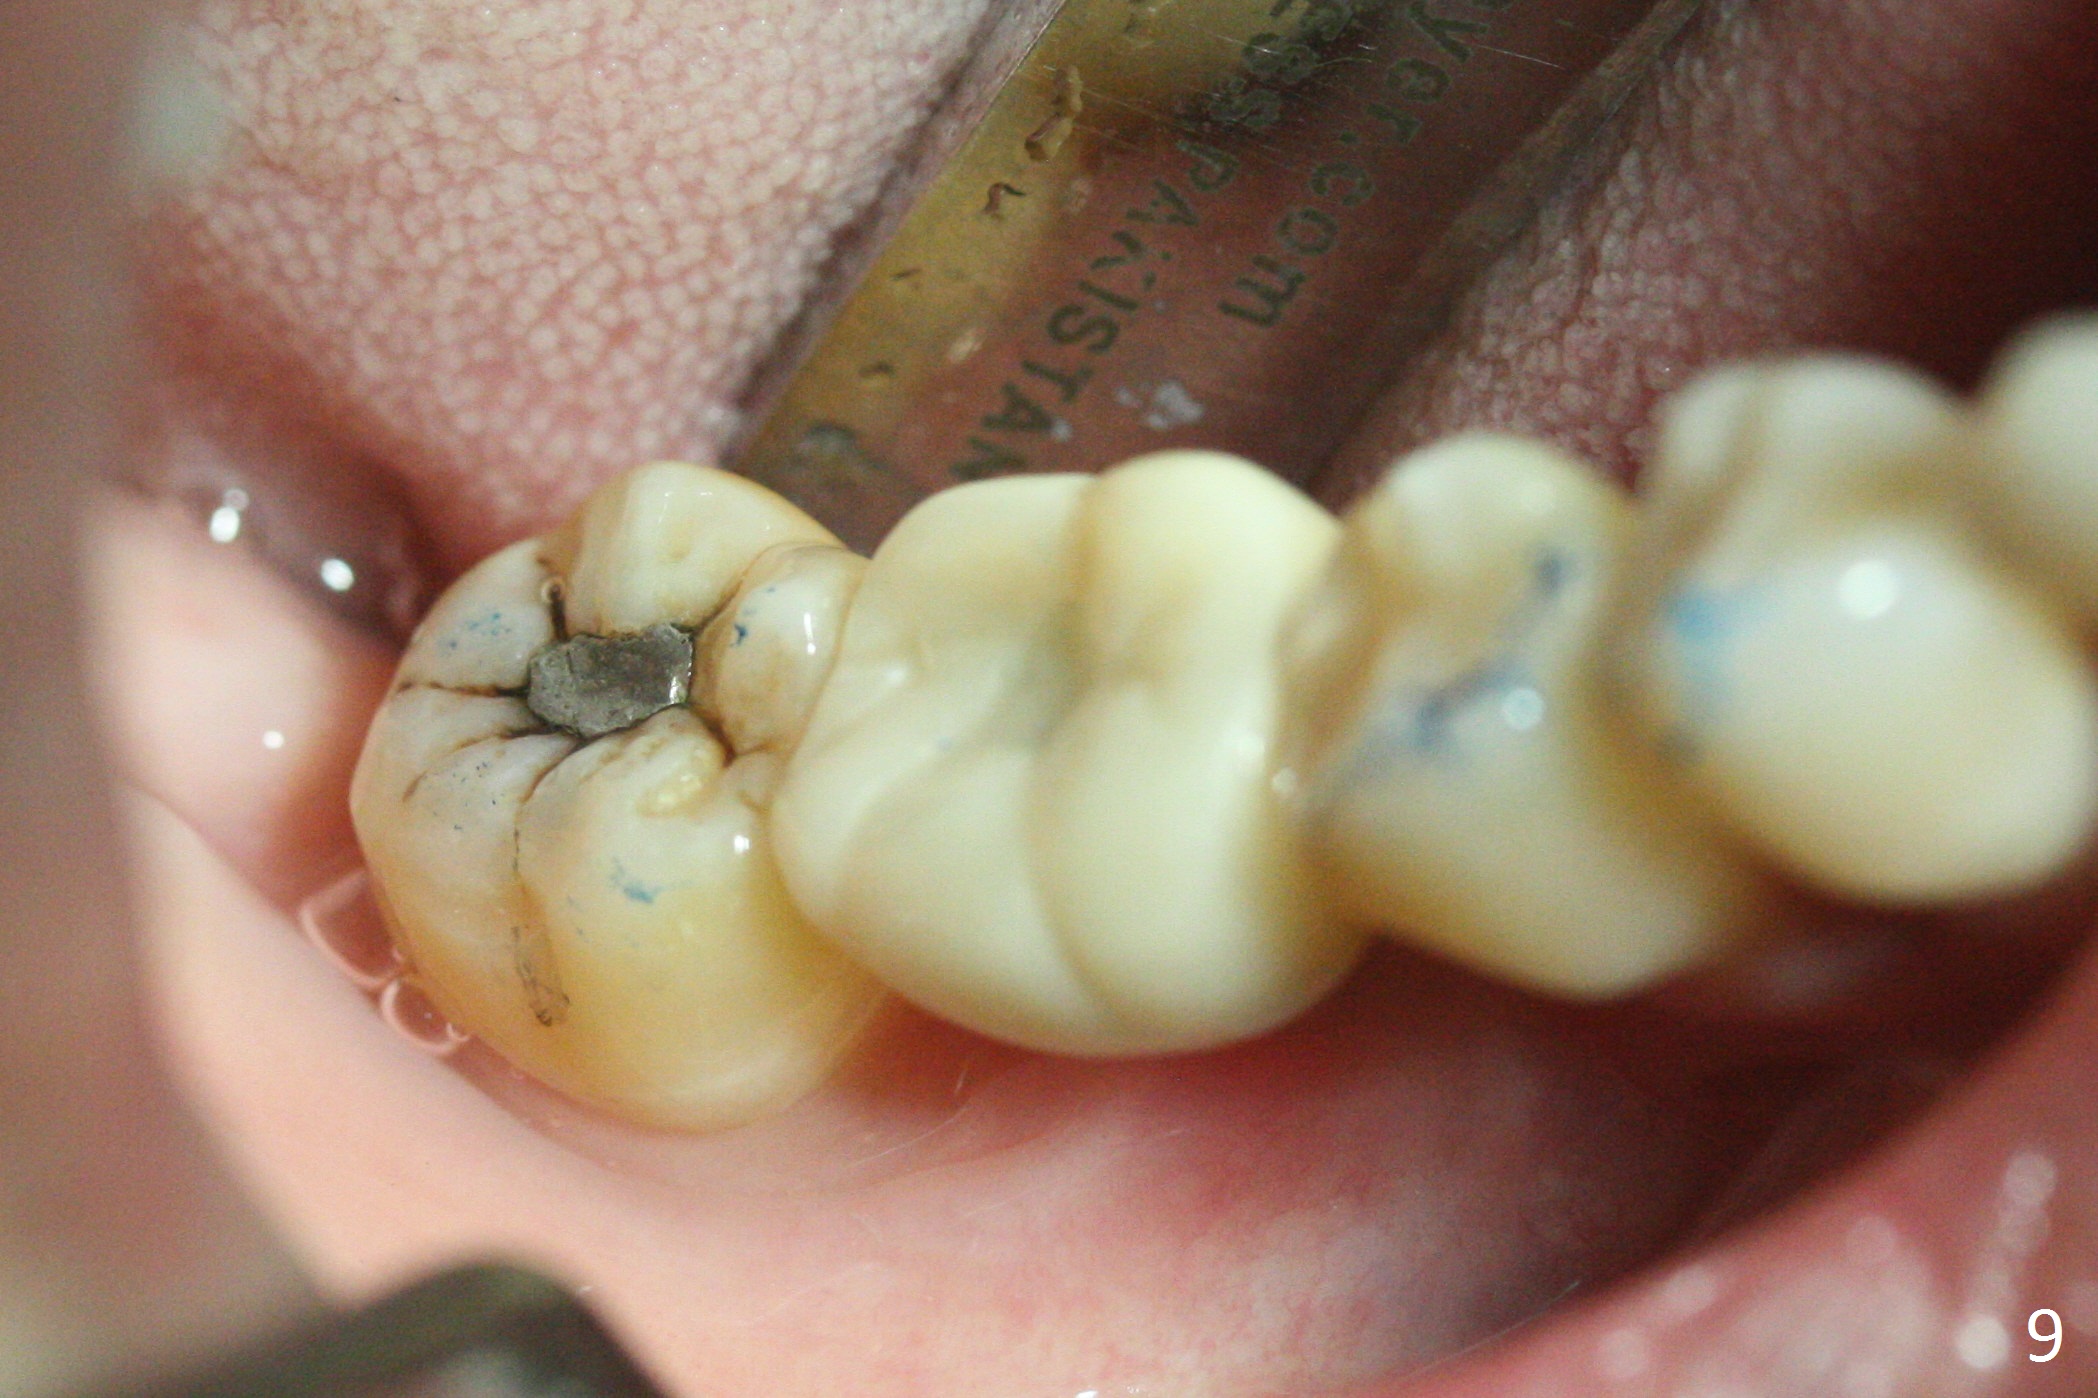

A provisional is fabricated 1 month postop to prevent the tooth #31 from rotation under the tension of the open coil spring, as mentioned above. Acrylic is added distal for #31 distalization nearly 2 months postop. More definitive orthodontic action begins 3 months postop (Fig.7, banding and open coil spring). The edentulous space increases to satisfactory width 3.5 months postop (Fig.8). A normal sized crown is delivered 4 months postop (Fig.9). The patient is pleased with the new tooth (Fig.10 nearly 6 months post cementation). There is no bone loss 13 months post cementation (Fig.11 (pan), 12 (CT coronal section (L: lingual))).